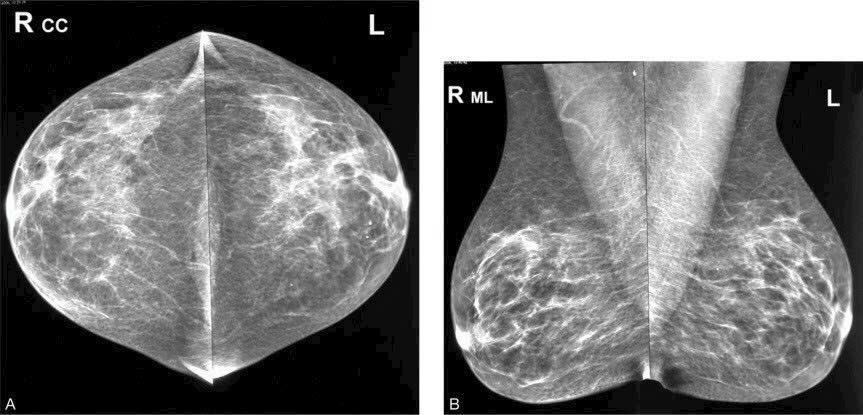

Khi Nghi Ngờ Một Bên Vú, Có Thể Chụp Một Bên X-quang Được Không?

Nhiều người có thể nghĩ rằng việc chỉ chụp một bên vú sẽ giúp tiết kiệm chi phí và giảm bớt lượng tia X phải tiếp nhận, tuy nhiên, việc này...